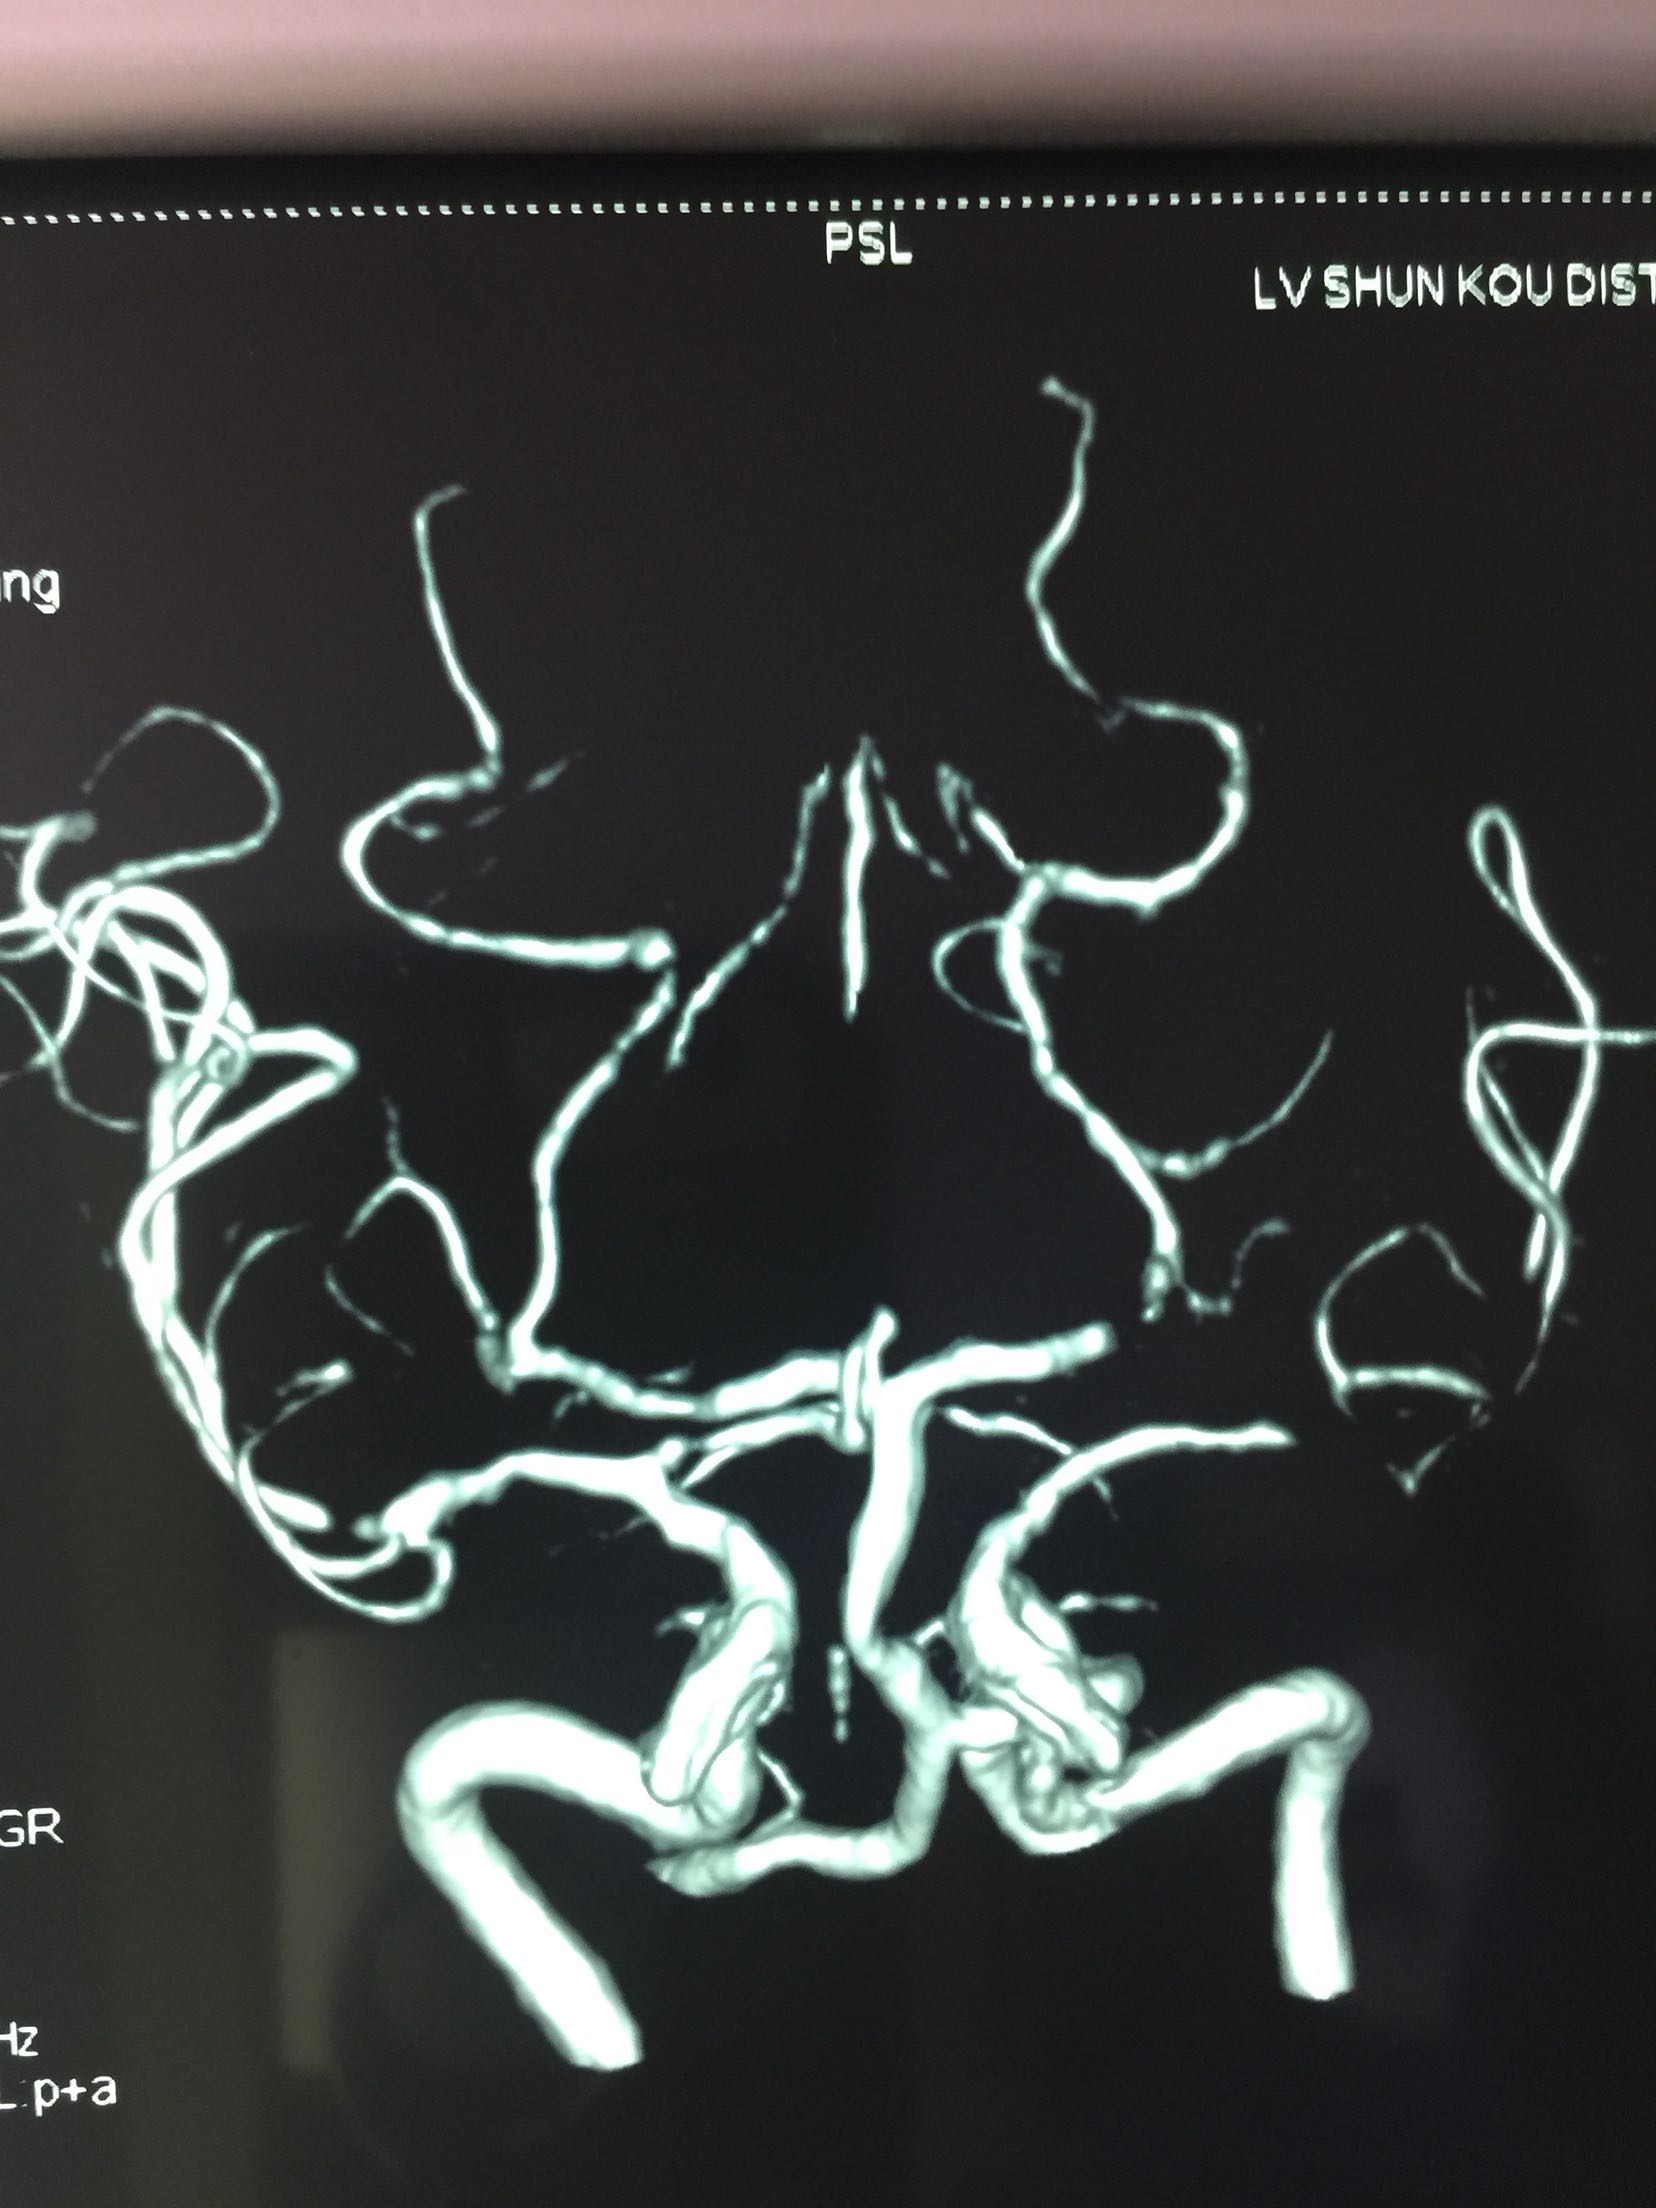

查体:T:36.5℃ P:68次/分 R:18次/分 Bp:120/70mmHg 内科系统:正常 神经系统:神志清楚,言语欠流利,查体合作,平车推人病房。左侧鼻唇沟浅,伸舌左偏,左侧肢体肌力0级,左侧肢体腱反射消失,左巴士征阳性。 辅助检查:血尿常规:正常 肝功、生化:正常 LDL-ch:5.12mmoL/l 心电图:窦性心律 头MRI+MRA、头CTA:

见下图